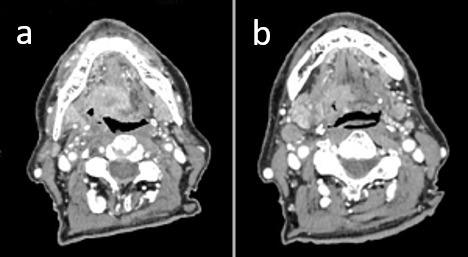

At presentation, isolated metastasis from oropharyngeal squamous cell carcinoma is rare. Liver is a relatively uncommon first site of failure, especially in the absence of other distant metastases, particularly without diagnosis of lung metastases. We report on a case of HPV-related oropharyngeal squamous cell carcinoma with synchronous liver metastasis treated with radiation therapy. This condition, defined as "oligometastatic state," describes a subset of patients with limited volume metastatic disease in whom favorable outcomes were reported with the use of local ablative therapies on both the primary tumor and metastatic sites. As a definitive treatment, we offered the patient, ineligible for other therapeutic approaches, exclusive radiation treatment on the head and neck region and a stereotactic ablative approach targeted to the liver metastasis.

摘要

就诊时,口咽鳞状细胞癌的孤立性转移很少见。肝脏是相对不常见的首个失败部位,尤其是在没有其他远处转移的情况下,特别是未诊断出肺转移时。我们报告了1例接受放射治疗的HPV相关口咽鳞状细胞癌伴同步肝转移的病例。这种情况被定义为“寡转移状态”,描述了一组转移病灶体积有限的患者,据报道,对这些患者的原发肿瘤和转移部位采用局部消融治疗可取得良好疗效。作为确定性治疗,我们为不符合其他治疗方法条件的患者提供了针对头颈部区域的单纯放射治疗以及针对肝转移的立体定向消融治疗。